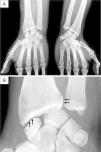

Plain radiography showed radio-carpal joint space narrowing, subchondral sclerosis of the joint margins, and linear calcifications of the distal radio-ulnar and radio-carpal joints (Fig. 2).